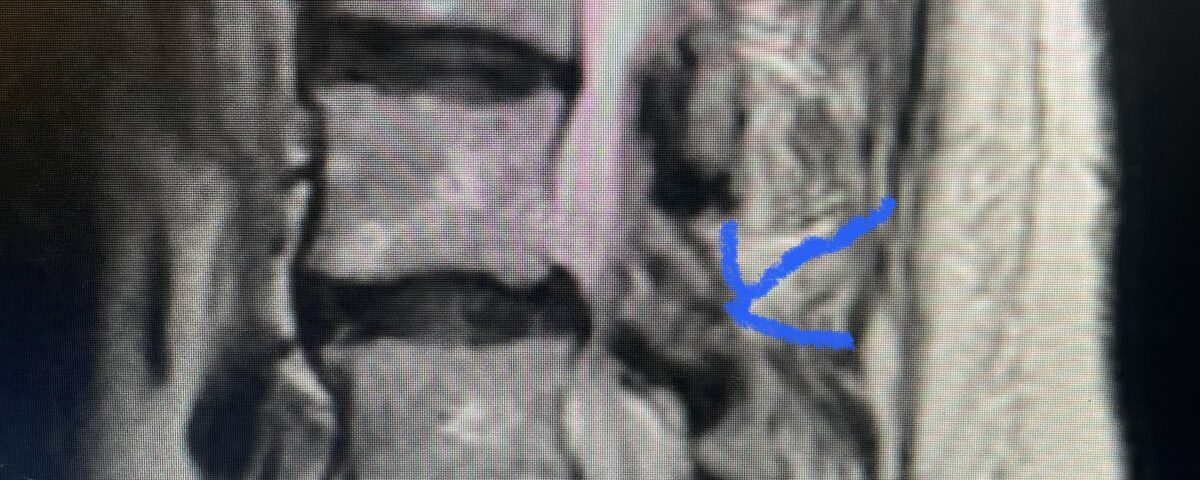

Another patient is a 62 year-old female with progressive low back pain and right leg pain and numbness that radiates to the top of her foot. She tried physical therapy and epidural injections. MRI demonstrated severe L3-4 stenosis and a grade 1 spondylolisthesis (Fig 4). There was L5-S1 and L4-5 disc collapse with modic end-plate changes. Biomechanically because of the significant degeneration of these disc spaces which stiffened the L4-S1 segment more stress was placed on the L3-4 segment, resulting in significant premature degeneration and compensatory stenosis and segmental instability. The MRI also showed pathologically, because of the slip, the L3 inferior processes were more anteriorly oriented and hence contributing to the majority of the lumbar canal compromise. Note the more sagittally-oriented facets in this case compared to the prior case (Fig 5). The patient underwent a decompressive laminectomy with attention of removing the inferior processes of L3 to fully decompress the canal. We also performed an L3-4 fusion with instrumentation (Fig 6). The patient had an uneventful postoperative course with improvement of leg pain. Of note with relief of the disabling leg pain patients are generally very happy. Patients can often manage their low back pain; it is the leg pain that they just can’t tolerate.

Fig 5 Axial T2-weighted lumbar MRI demonstrating significant L3 inferior facet contribution of severe stenosis (blue arrow)